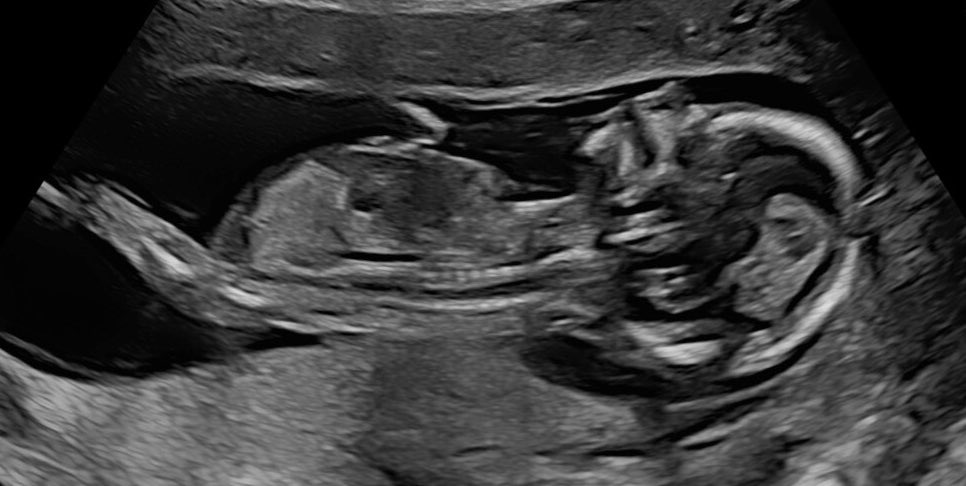

This is a baby 8 weeks from fertilization, 10 weeks LMP. This is the baby the abortion industry claims is a "clump of cells." This is the baby targeted by the abortion pill. Every child deserves a chance at life. Every child deserves to be protected. Ban abortion NOW.